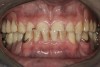

Initial examination revealed a partial edentulous patient with extensive wear of the maxillary anterior teeth and moderate wear in the mandibular teeth (Figure 1, Figure 2, Figure 3 , Figure 4, Figure 5, Figure 6 and Figure 7). The patient's maxillary and mandibular RPDs also showed excessive wear and multiple signs of fractures (Figure 2 and Figure 3). The patient had been wearing a mandibular nightguard for 8 years.

Figure 2  Intraoral occlusal view of maxillary dentition with the existing removable prosthesis presenting excessive signs of wear.

Figure 2